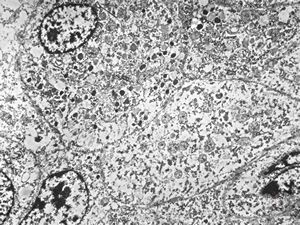

F,31y. | mucoepidermoid carcinoma

F,31y. | mucoepidermoid carcinoma

F,31y. | mucoepidermoid carcinoma

F,31y. | mucoepidermoid carcinoma